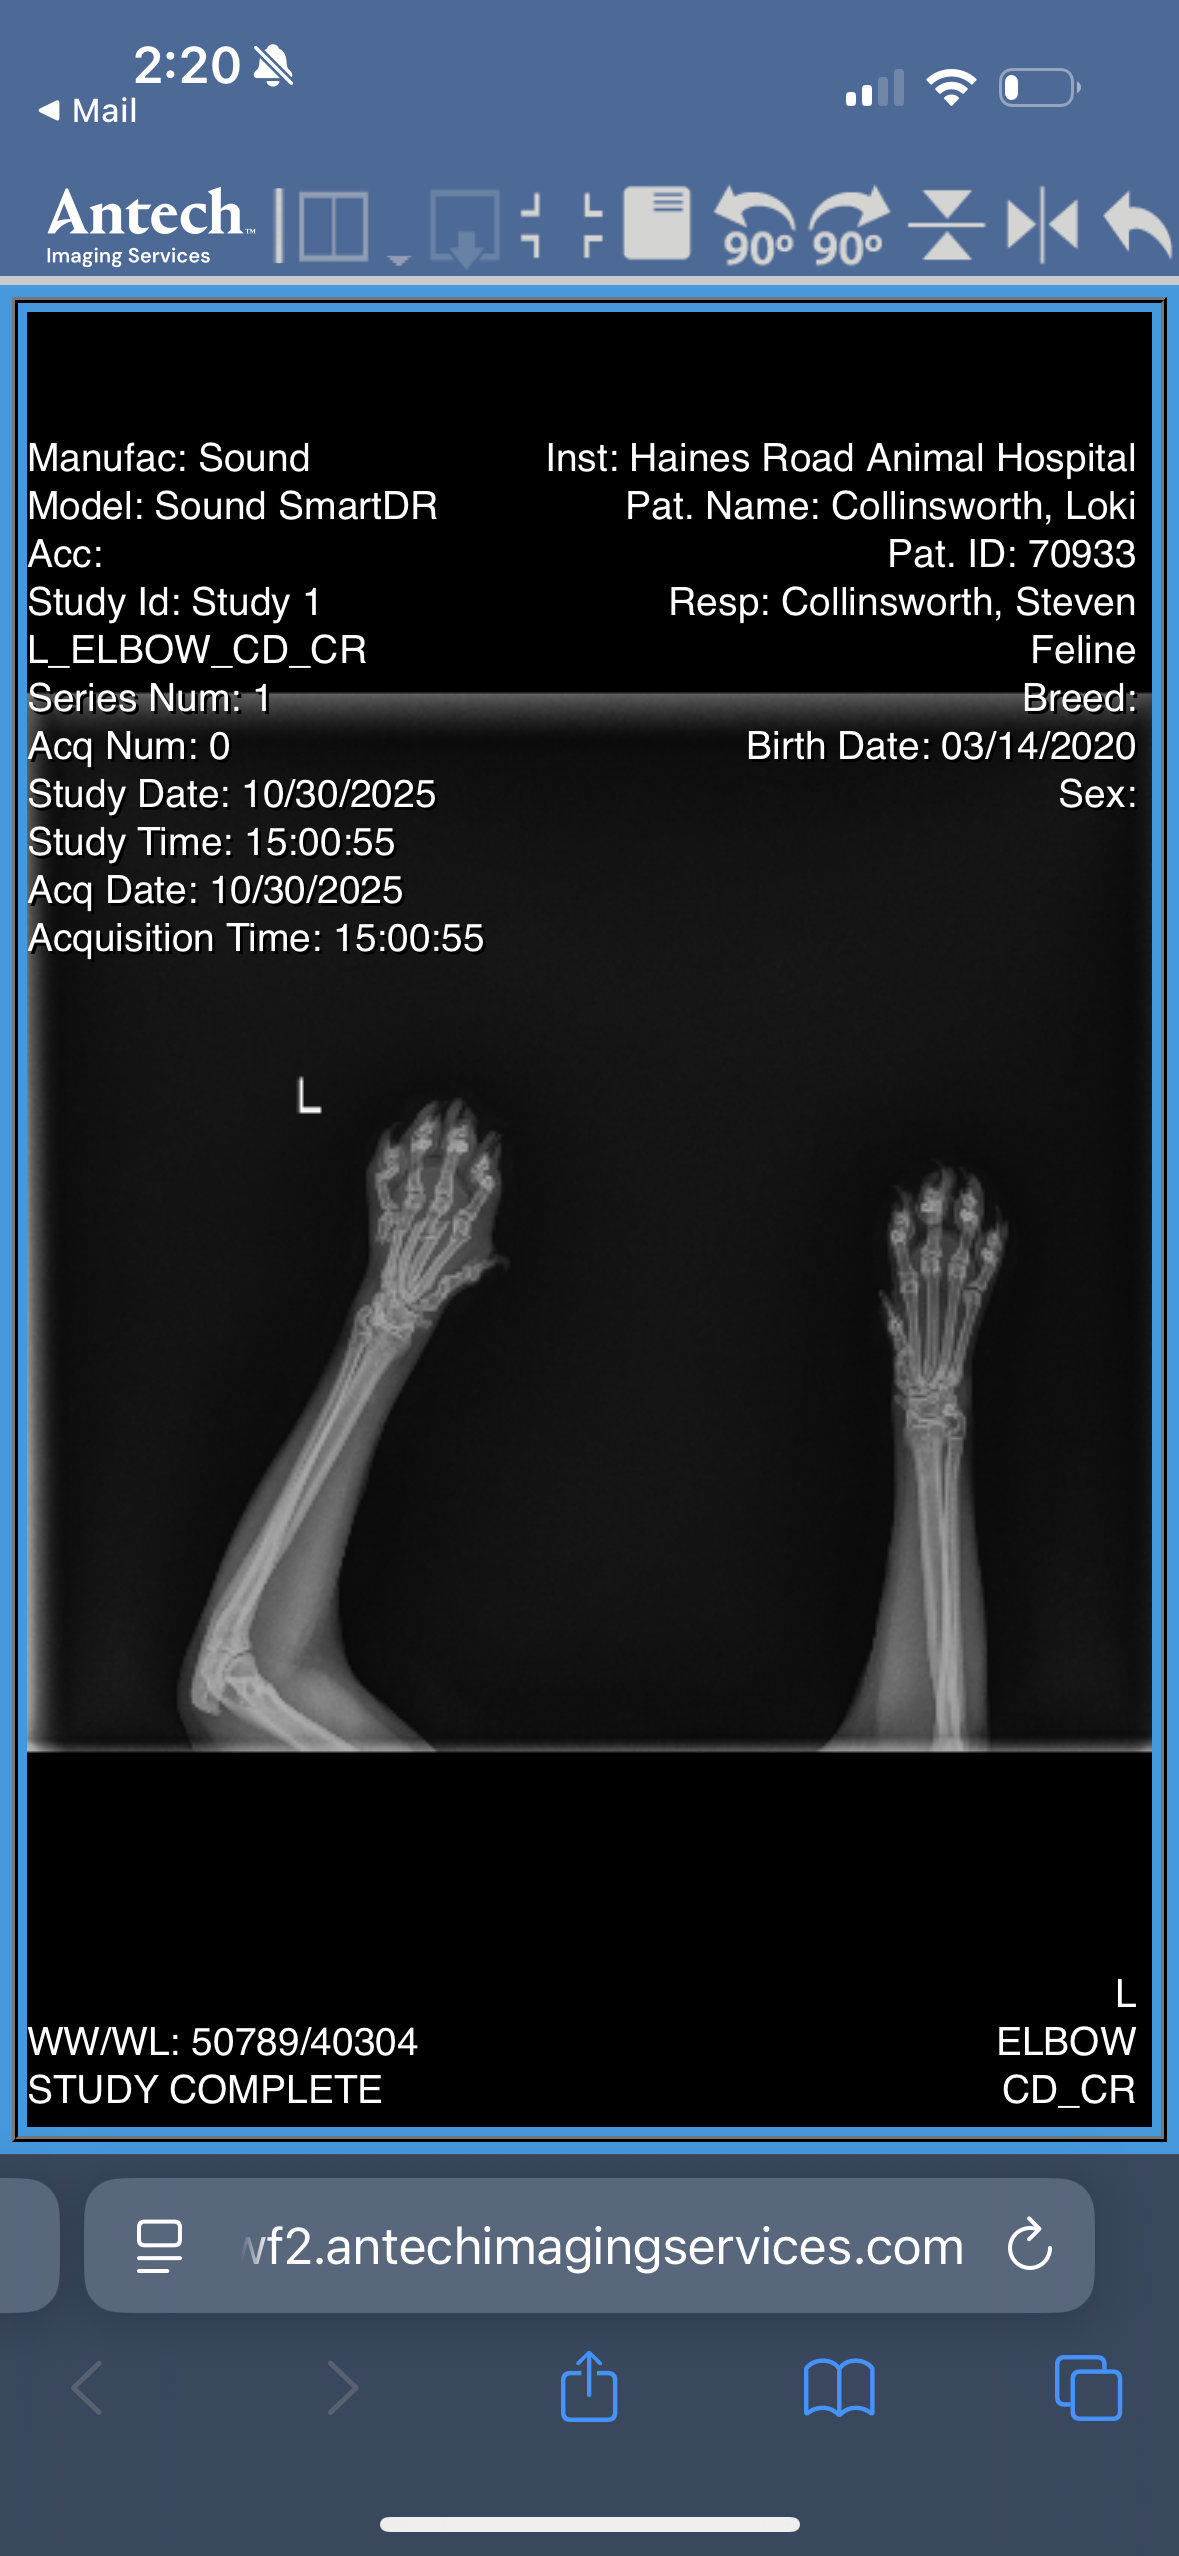

A few days ago, something awful happened. Loki accidentally smashed his paw under a falling table, breaking every one of the bones in his foot. My heart broke seeing him in so much pain. When I rushed him to the vet, they told me something I never expected to hear:

because of where the break happened — in his paw — the usual way to fix it isn’t possible. Cats can’t just have the paw repaired or partially amputated. Normally, the only option would be to remove the entire leg.

But Loki’s vet has been absolutely incredible — they truly put him first. After seeing the x-rays, the vet consulted with a specialist to see if there was any way to save his leg. Miraculously, the specialist said he can perform an emergency surgery to place pins in Loki’s toes and repair the bones.

That surgery would give Loki the chance to walk again on all four paws. Without it, the only option left would be a full amputation — but because Loki is a big boy, he wouldn’t adapt well to life on three legs. His vet made it clear: they’re trying to save his leg because they know how hard it would be for him to recover otherwise.

Loki is being treated by Dr Sharp at Haines Road Animal Hospital in St Petersburg, FL and the orthopedic surgery would be performed by Dr Curry at Epic specialty and emergency pet care. Both have been incredible advocates for him and have confirmed that surgery must happen as soon as possible to save his leg. I can verify the diagnosis, the urgency, and the surgical estimate if needed.